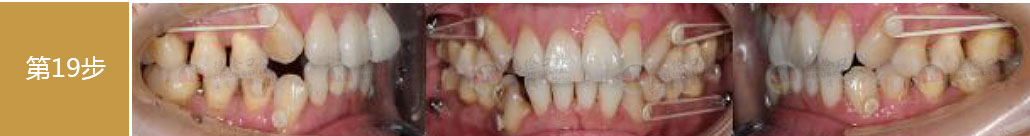

矯治前后對(duì)比

蛻變周期:上頜16個(gè)月,矯治效率提升30%,下頜12個(gè)月,矯治效率提升20%